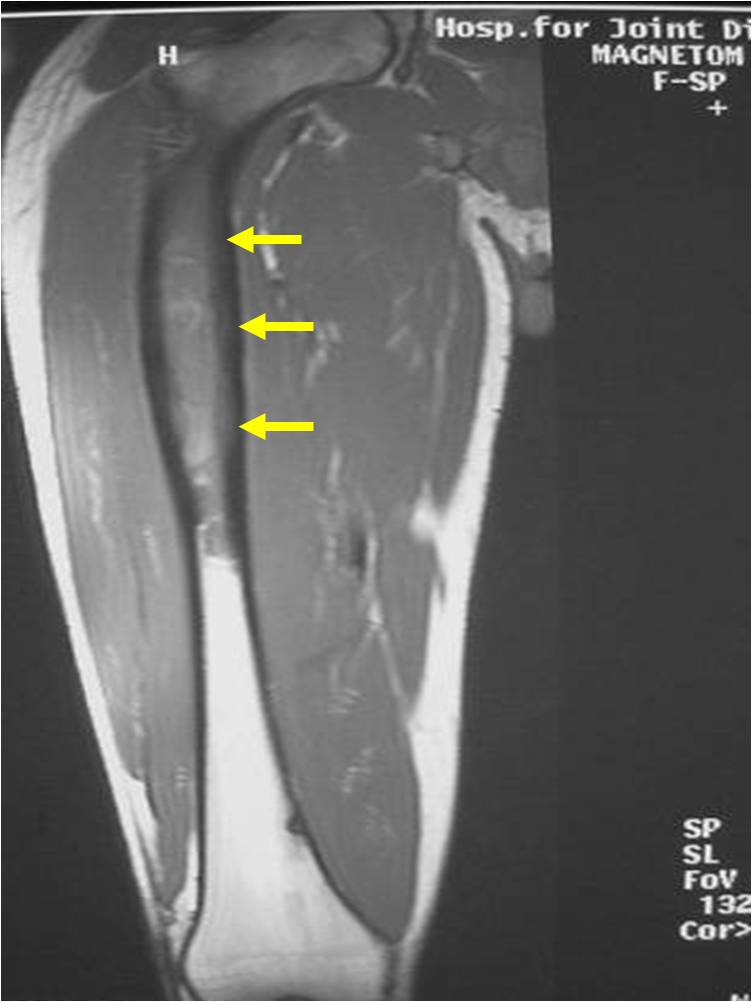

- Soft Tissue Mass in 90% of of cases

- Ewing sarcoma responds well to chemotherapy. Often there is a dramatic reduction in size of the tumor.

- Lesions grossly confined to bone have a better prognosis than those with a soft tissue component

- Response to preoperative chemotherapy: Greater than 90% tumor necrosis (Good response) correlates with a better prognosis

- Tumors greater than 8cm in maximum dimension and those with greater than a volume of 100cc have been associated with a worse prognosis